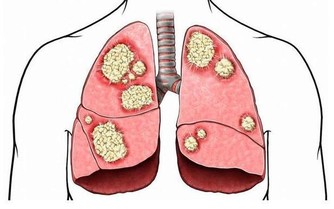

對於菸熏油炸燒烤食物當中含有苯並芘、丙烯酰胺,這些物質屬於致癌物質,會導致胃病和胃癌的出現,所以胃不好的人要遠離這些食物。

如果前列腺素E2含量減少,就容易患上胃炎,胃潰瘍,甚至是胃癌。而且一些醃製食品當中含有的亞硝酸鹽會在體內轉換成亞硝胺,這種物質是誘發胃癌的危險誘因。

進而會引起這些部位出現水腫,充血和糜爛,甚至是潰瘍的現象。患有胃炎和胃潰瘍的人吃辣椒會導致胃部粘膜受到破壞,提高患上胃癌的機率。